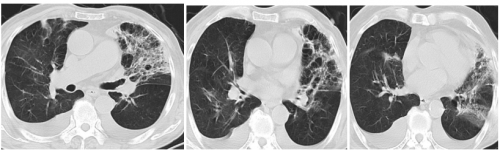

10.28 当地复查医院复查肺ct 如下 显示双肺多发斑片状影明显吸收好转。患者可正常活动。